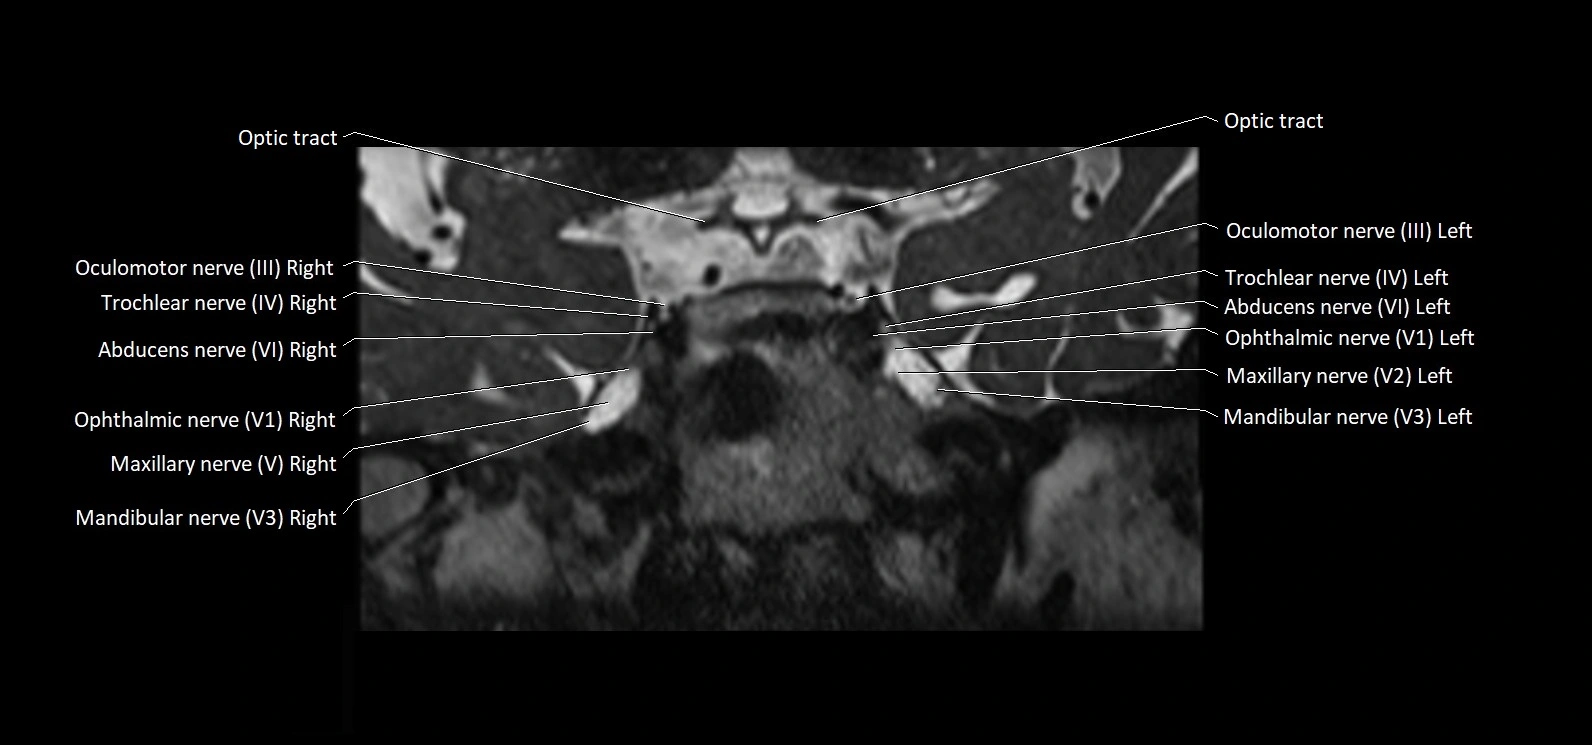

MRI Appearance

• The abducens nerve is a small, thin, linear structure

• Best visualized on high-resolution T2-weighted 3D MRI sequences (e.g., FIESTA or CISS)

• Seen as a hypointense (dark) line running from the brainstem at the pontomedullary junction, traversing the prepontine cistern, and entering Dorello’s canal under the petrosphenoidal ligament, then into the cavernous sinus, and finally the orbit

• May be challenging to visualize in standard MRI due to its small size

• Pathology may be inferred by absence, displacement, or enhancement of the nerve